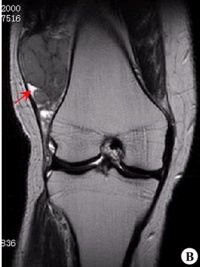

滑膜肉瘤是发生频率较高的一种软组织肉瘤,好发于15-40岁,四肢的大关节附近,特别是膝关节附近好发,另外与关节无关的部位如头颈部、腹壁、后腹膜也可发生。本病的基本X线表现有三点:软组织肿块,局部骨皮质破坏,肿瘤的钙化和骨化。此病好发于关节附近,呈分叶结节状,密度增高,边界清楚的软组织肿块。其内可见骨化影,呈条状或块状轮廓清楚的高密度影,部分骨化影中可见骨小梁结构,少数病例为骨化性肿块。应与骨旁骨肉瘤、骨化性肌炎、骨肉瘤等鉴别。

(1)软组织肿块。临床所能触及的肿块并不都在X线上显示出来。有的表现局部软组织肿胀,有的出现软组织肿块。一般肿块密度较邻近软组织稍高,大小不等,小的只有豌豆大,大者可巨大,有跨越关节生长的特点。

(2)软组织肿块钙化。软组织肿块内可见到不定形、不规则钙化影,占30%。钙化的原因可能与出血、感染、坏死及软骨钙化等有关,且钙化的多少与肿瘤恶性度有关,钙化越少,恶性度越高。

(3)骨骼改变。会出现不同程度骨质压迫、缺损或溶骨性破坏。譬如骨质疏松,骨萎缩畸形,囊性骨缺损,骨质糜烂,溶骨性破坏,关节改变。骨质轻度疏松为早期表现,以后压迫性骨萎缩、变细或囊性缺损,进一步发展出现骨质破坏。骨破坏大多呈不规则状,也可呈囊状,跨关节者可侵及多骨。本病一般关节无改变,但偶尔可有侵入关节,使间隙增宽或出现软组织肿块,也可出现关节积液,易误诊为关节疾患。

(4)骨膜反应。可出现平行、花边状或针状骨膜反应,有些虽未见到明确骨膜反应,但邻近骨皮质可见到刺状突起。可能出现Codman三角。